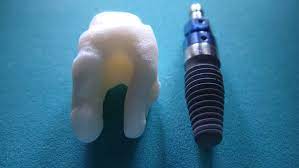

임플란트란

임플란트는 충치, 잇몸병으로 인해 상실된 치아나 사고와 종양으로 없어진 치아의 기능과 미용을 복원하기 위해 치료하는 시술을 말합니다. 임플란트는 통증, 움직임이 거의 없는 나의 치아와 같은 느낌을 주며 입안의 뼈가 건강하다면 80세 이상까지도 치료가 가능한 시술이라고 할수 있습니다.